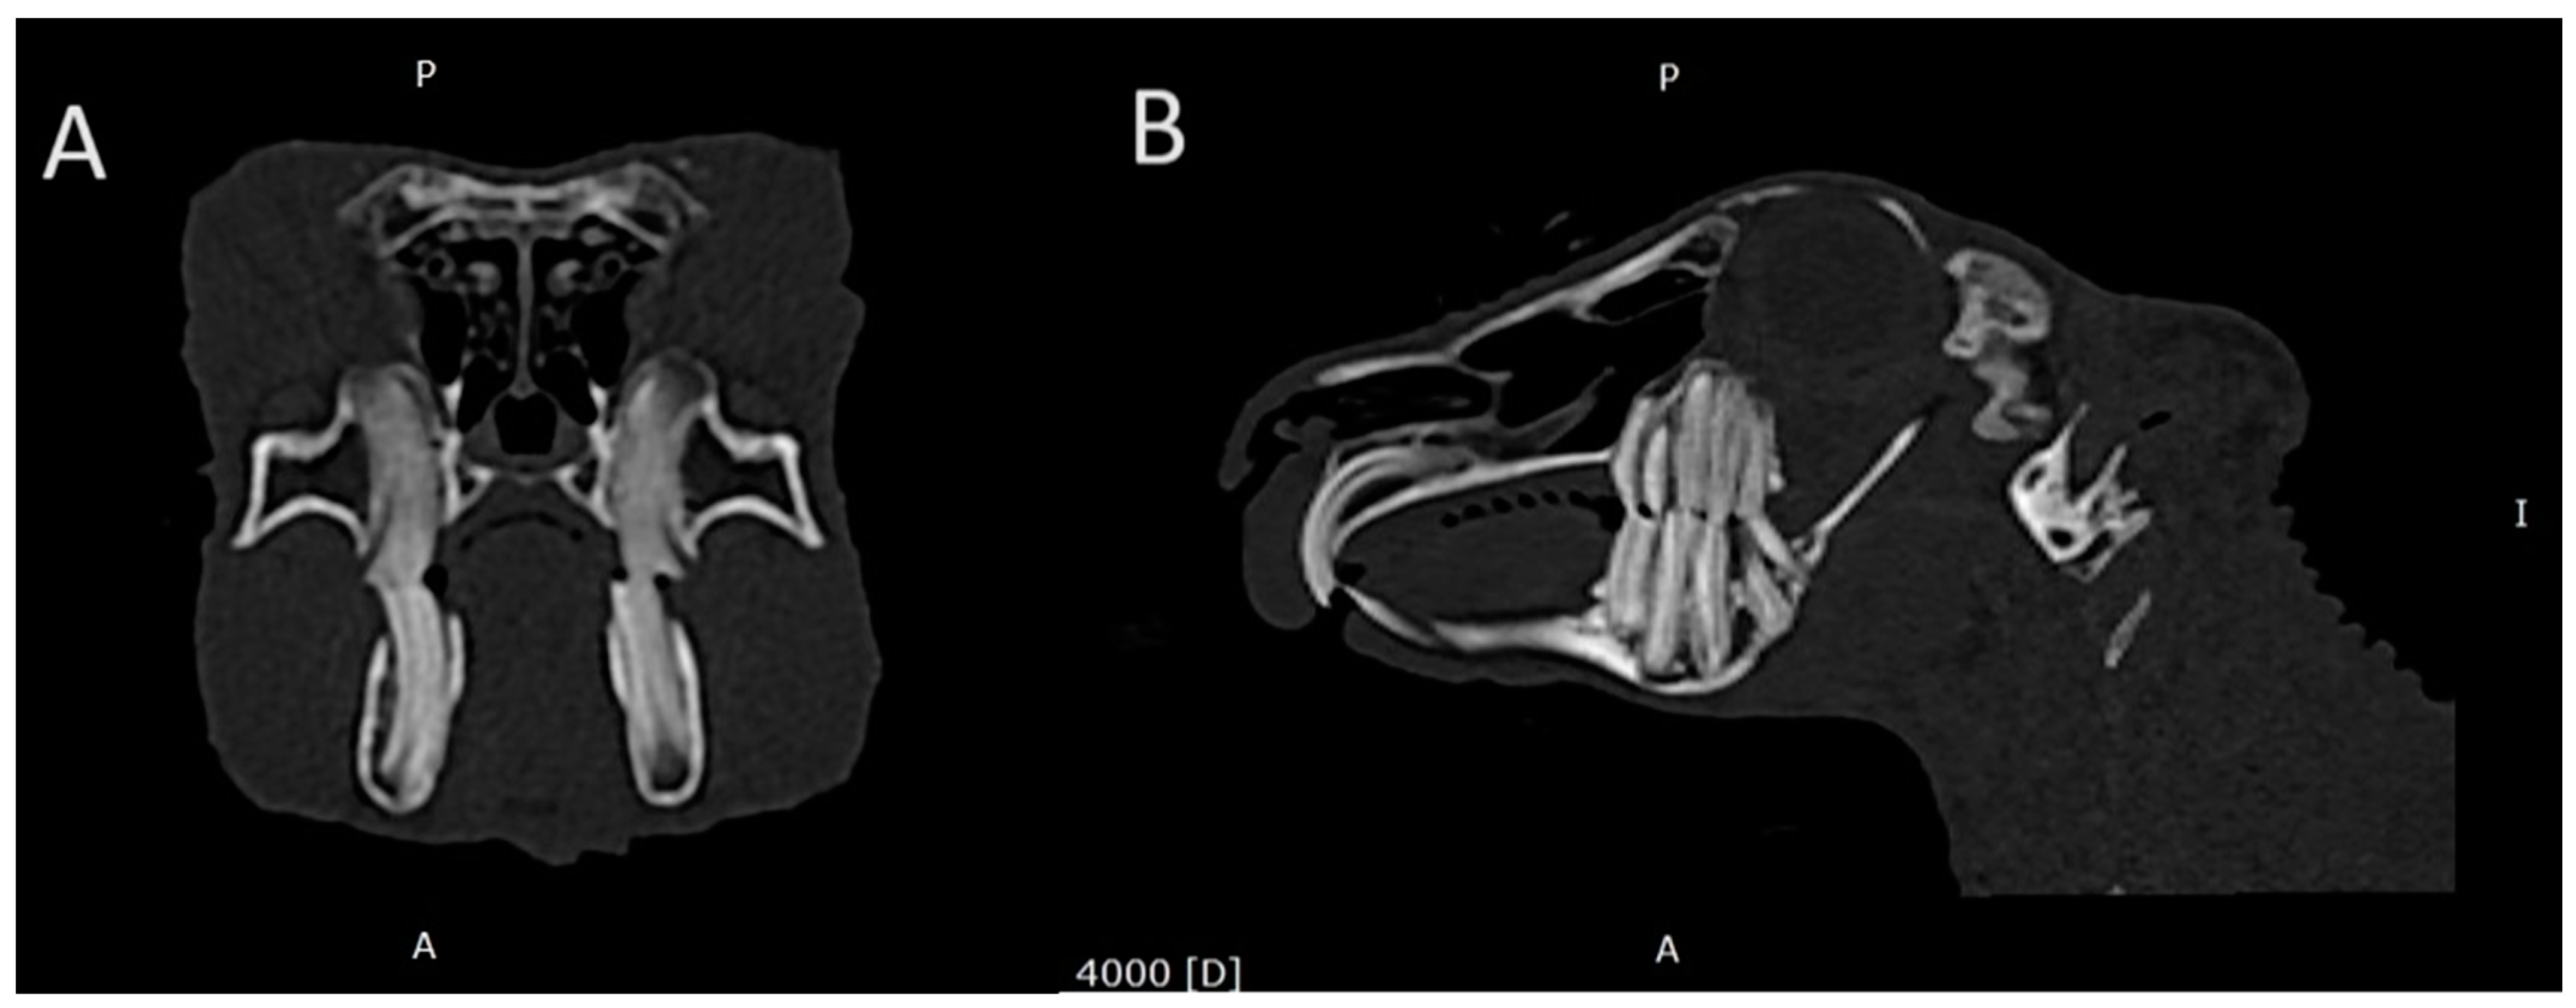

3.3. Prevalence of Retrograde Apical Elongation in the Maxilla and Bone Deformities Secondary to It

3.4. Prevalence of the Clinical Crown Overgrowth of Teeth in the Maxilla and Mandible